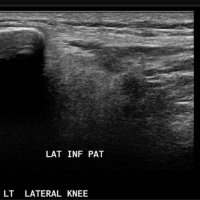

PATELLAR TENDON-LATERAL FEMORAL CONDYLE FRICTION SYNDROME

Patellar tendon-lateral femoral condyle friction syndrome, also known as Hoffa fat pad impingement syndrome, is a common cause of anterior knee pain in active individuals. It is thought to be due to patella maltracking or imbalance of the forces between medial and lateral vastus muscles causing impingement of the superolateral aspect of Hoffa fat pad between the inferior patella and the lateral femoral condyle.

Patients with Hoffa syndrome would present with acute or chronic sharp pain below the patella which is worsened by activities like walking, prolonged standing, wearing high heel shoes or any other activity that puts the knee into full extension. On examination, there may be swelling in the infrapatellar region, with point tenderness at the inferior pole of the patella.

The diagnosis is classically made with MRI and usually occult on radiography and CT. MRI findings include focal area of high T2 signal (edema) at the inferolateral aspect of the patellofemoral joint, within the superolateral portion of the infrapatellar fat pad. A cystic lesion can sometimes be found between the lateral femoral condyle and the lateral retinaculum. Associated findings include lateral patellar subluxation and patella alta (Insall-Salvati ratio greater than 1.2) which are found in around 90% of cases. Conservative treatment is usually successful, although full recovery may take time.